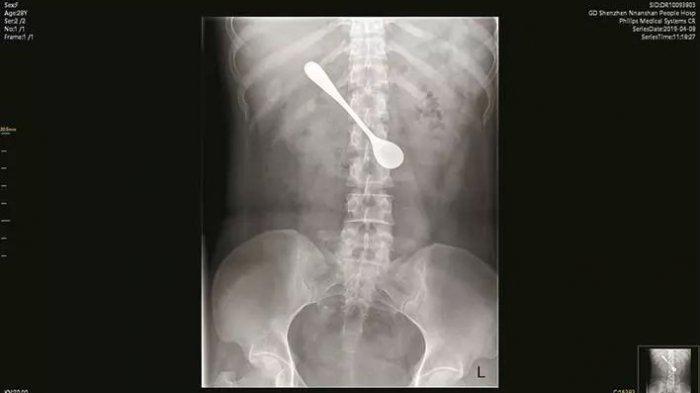

Ketika dilakukan X-ray terlihat sebuah sendok logam besar tersangkut di duodenumnya.

Dr Sun Tingji melalui Pear Video mengatakan bahwa posisi sendok berada agak horizontal sehingga para dokter harus berhati-hati ketika akan menariknya keluar.

Selain itu, sendok logam yang tertelan itu juga menyebabkan pembengkakan dan erosi pada duodenum pasien.